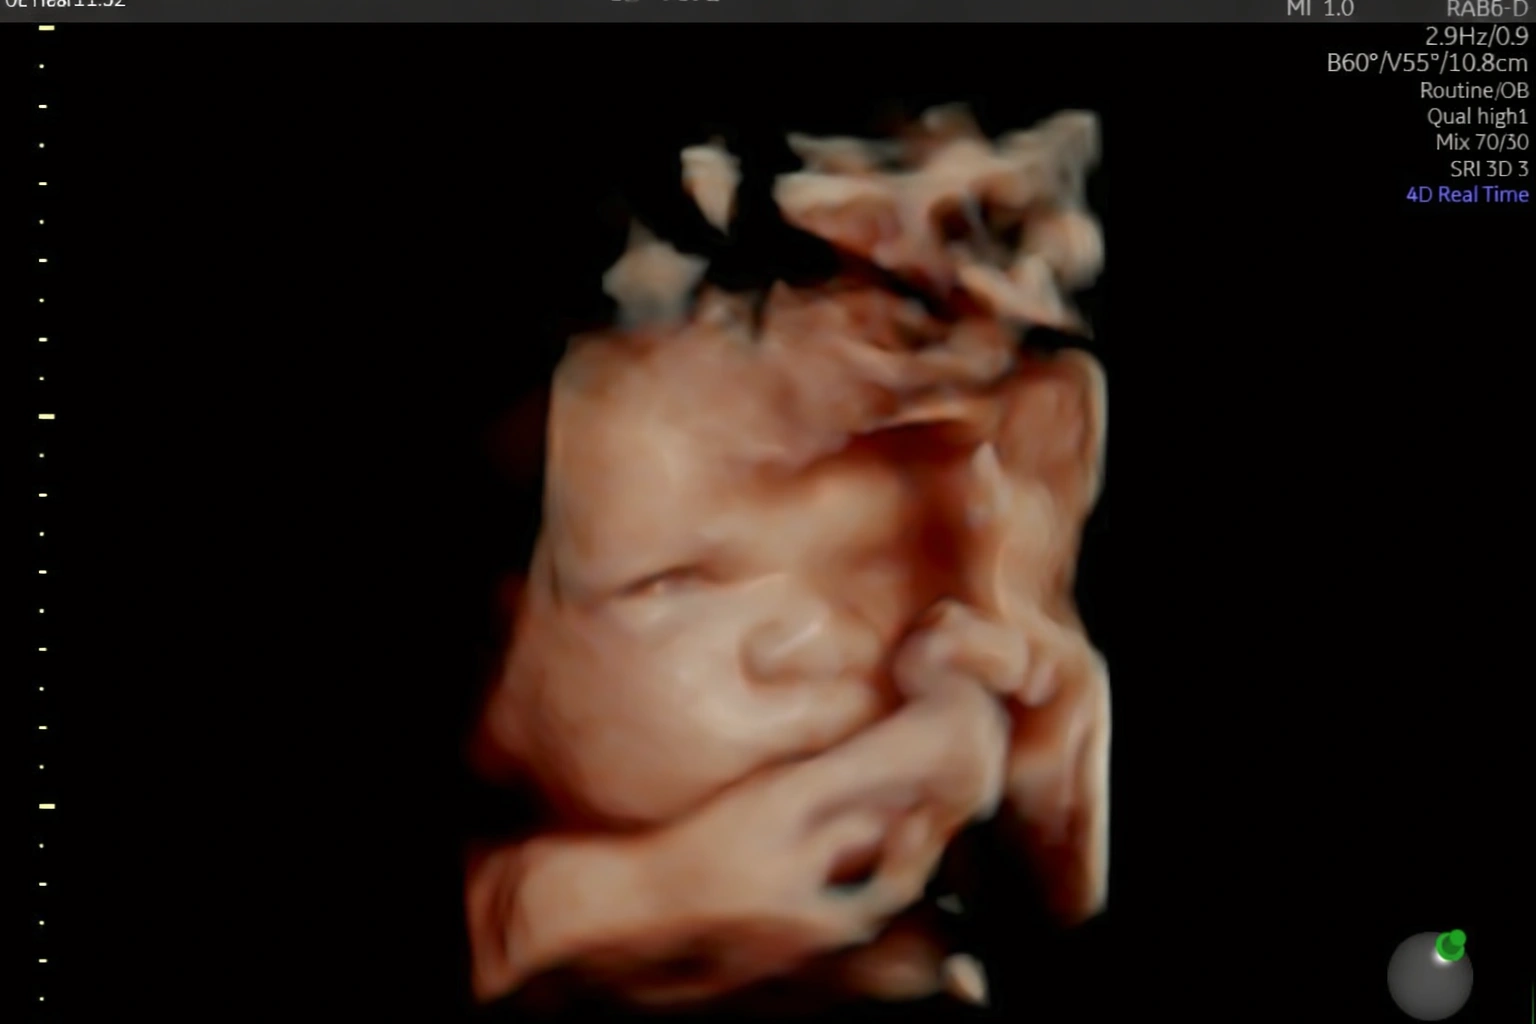

Acompanho detalhadamente toda a evolução do seu bebê ainda na sua barriga.

Realizo diversos tipos de ultrassonografia para garantir que seu bebê chegue ao mundo com saúde.

Estou pronta para realizar diagnósticos precisos sobre como anda a saúde do seu bebê ainda ai dentro da sua barriga. Realizo toda e qualquer tipo de ultrassonografia obstetríca.